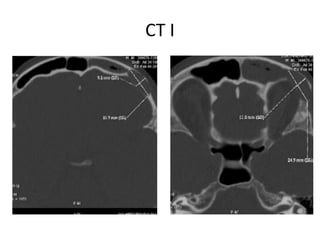

CT

CT I

CT II

Citas sūdzības: • Periodiskadeguna obstrukcija • Elpošanas grūtības caur degunu • Izdalījumi no deguna • Spiedošas sāpes kreisajā sejas pusē (īpaši izteiktas supraorbitāli, frontāla dobuma projekcijas vietā)  CT  MRI